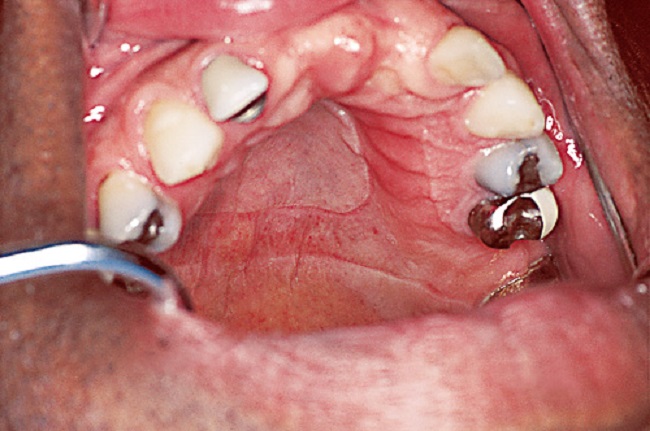

14Denture thrush and stomatitis

Poor hygienic practices involving your dentures or not removing them at night can lead to infections in your mouth such as stomatitis, thrush or yeast infections. This will never happen with dental implants as they are a single tooth covering a screw and you can brush them like regular teeth.